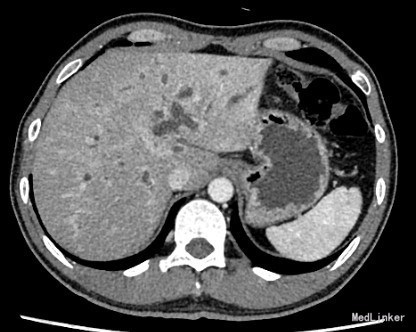

查体:身目重度黄染,上腹部轻压痛; 辅助检查: 白细胞WBC:10.96; 血红蛋白Hb:145g/L;血小板PLT:241x10^9/L 丙氨酸氨基转移酶ALT 357 U/L ;天冬氨酸氨基转移酶AST 191 U/L;白蛋白ALB 40.9 g/L ;总胆红素TBIL 151.2 umol/L;直接胆红素DBIL 85.8 umol/L 肿瘤标记物: 甲胎蛋白(AFP) 5.00 ug/L 0.00 - 20.00 ;癌胚抗原(CEA) 9.19 ug/L ↑ 0.00 - 5.00 ;CA125 71.00 U/mL ↑ 0.00 - 35.00 鳞癌抗原(SCC) 0.90 ug/L 0.00 - 1.50 ;CA19-9 〉12000.00 U/mL CT:平扫胰体尾部萎缩,胰头区不规则肿大,局部可见类圆形软组织肿块影,大小约44×43mm,边界模糊,内部密度不均,其内可见斑点状钙化灶,并见更低密度区。增强扫描正常胰腺组织明显强化而肿物轻度强化,显示较清楚;强化不均匀,中央有低密度坏死区。肿块与十二直肠降段分界不清,病变包绕肠系膜上静脉,血管见充盈缺损影,胰头周围及腹膜后见肿大的淋巴结影。、、、 1.胰头癌,侵犯十二指肠降段及肠系膜上静脉,胰周及腹膜后多发淋巴结轻度肿大。 2.肝S7病灶,高度怀疑转移瘤。 超声造影提:胰头病变:考虑胰头Ca。 肝S7病变:考虑MLC。 肝内外胆管弥漫性扩张。胆囊壁增厚。腹膜后淋巴结肿大。脾脏超声检查未见异常。